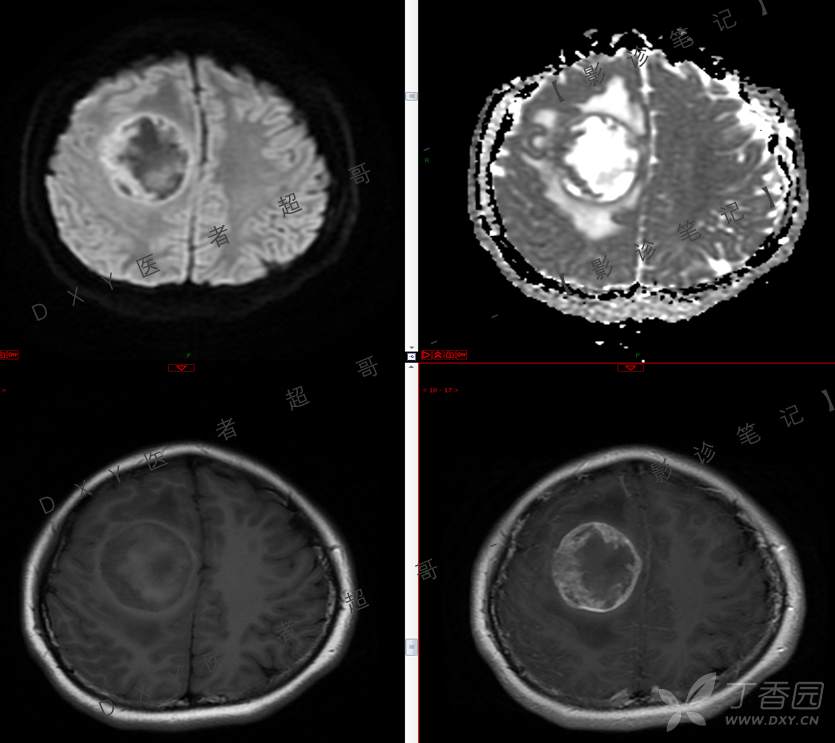

15岁少年,头痛10天,加重伴恶心、呕吐2天,究竟为何?回帖即可查阅病理。

患者年龄:15岁

主 诉:头痛10天,加重伴恶心、呕吐2天。

现病史:患者10天前无明显诱因出现头痛,间断发作,无恶心、呕吐,无肢体抽搐等,于当地医院就诊,体温37.4度,予以对症治疗,具体不详,后症状缓解,2天前患者上述症状较前加重,并感双眼胀痛及视物模糊,伴恶心、呕吐,呕吐数次,为胃内容物,再次于当地医院就诊,行颅脑CT考虑“右侧额顶叶病变”,现为求进一步治疗来我院急诊就诊,以“脑脓肿?”收入我科。患者病来精神差,饮食、睡眠欠佳,体重无明显变化。